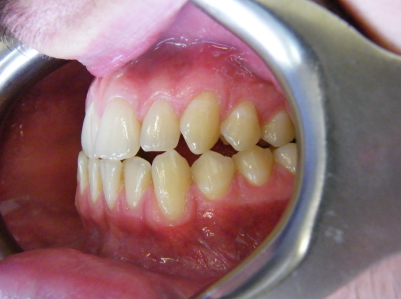

Patient 4: Upper and lower crowding, edge to edge bite and crossbite.